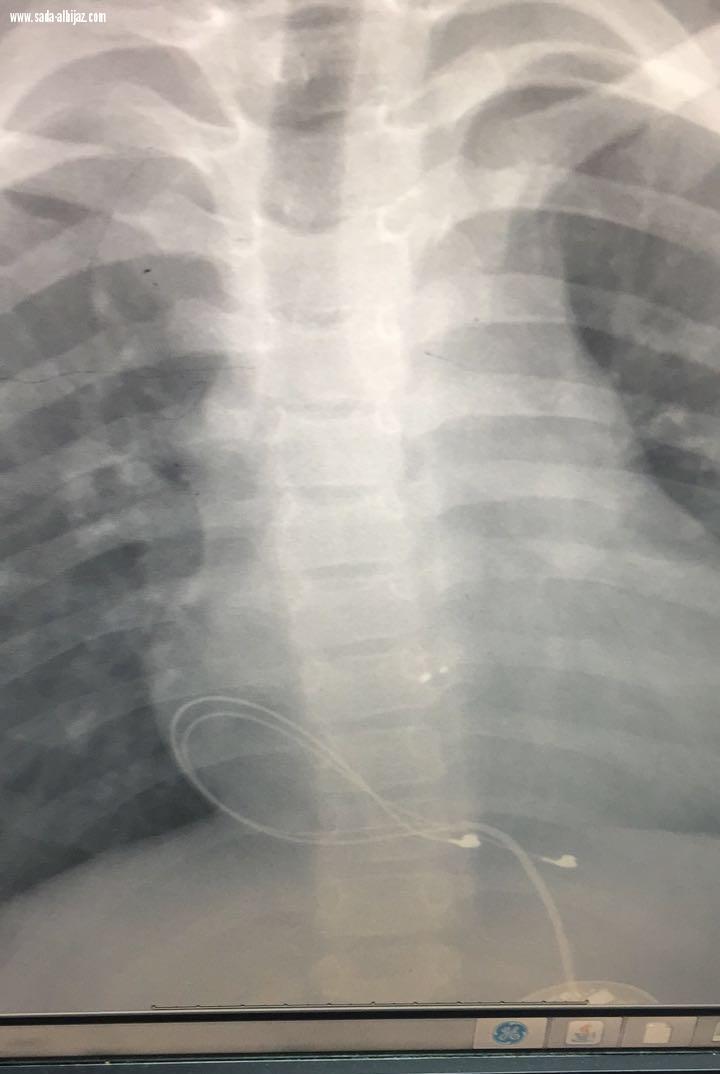

وبالكشف عليه من قبل المختصين من مركز القلب تبين خروج السلك الموصل بالقلب عن مكانه مع إمكانية وجود كسر فيه ، مما أثر سلبياً على ضربات القلب حيث تم التدخل السريع لإجراء عملية جراحية لإزالة السلك المكسور وزرع منظم جديد من قبل جراح قلب اطفال د محمد قنديل والاستشاريون المختصون في قلب الأطفال حيث تمكن جراحي القلب من السيطرة على الوضع بفضل من الله تعالى وعادت ضربات القلب لوضعها الطبيعي وحالة الطفل مستقرة بفضل من الله "